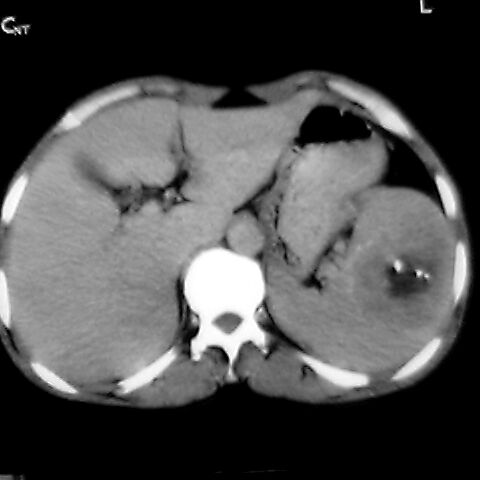

女 48岁 食道癌术前体检发现脾占位。

脾胀内部巨大低密度肿块,边界清或不清,中心坏死,轻度增强,内见散在钙化,结合食道癌病史多考虑:转移癌.

脾脏低密度灶伴钙化,增强化明显,中心见液化坏死灶,强化延时明显。考虑血管瘤。转移瘤待排。